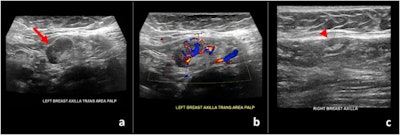

In one case, a 59-year-old woman with no personal history of breast cancer came to the department after finding a palpable lump near her left armpit. Her mammogram was unremarkable, but targeted sonography showed her left axillary lymph node had uniform cortical thickening of 0.7 cm in an area corresponding to the patient's concern.

When asked about her history, the patient said she had recently received the Pfizer-BioNTech COVID-19 vaccine and noticed the lump nine days after receiving her first vaccine dose.

The authors reported similar findings in two women who presented for routine breast ultrasound screening, as well as one woman who underwent ultrasound follow-up of probably benign bilateral breast masses. All three of these women had diffuse cortical thickening in at least one axillary lymph node within 13 days of receiving a first or second vaccine dose.